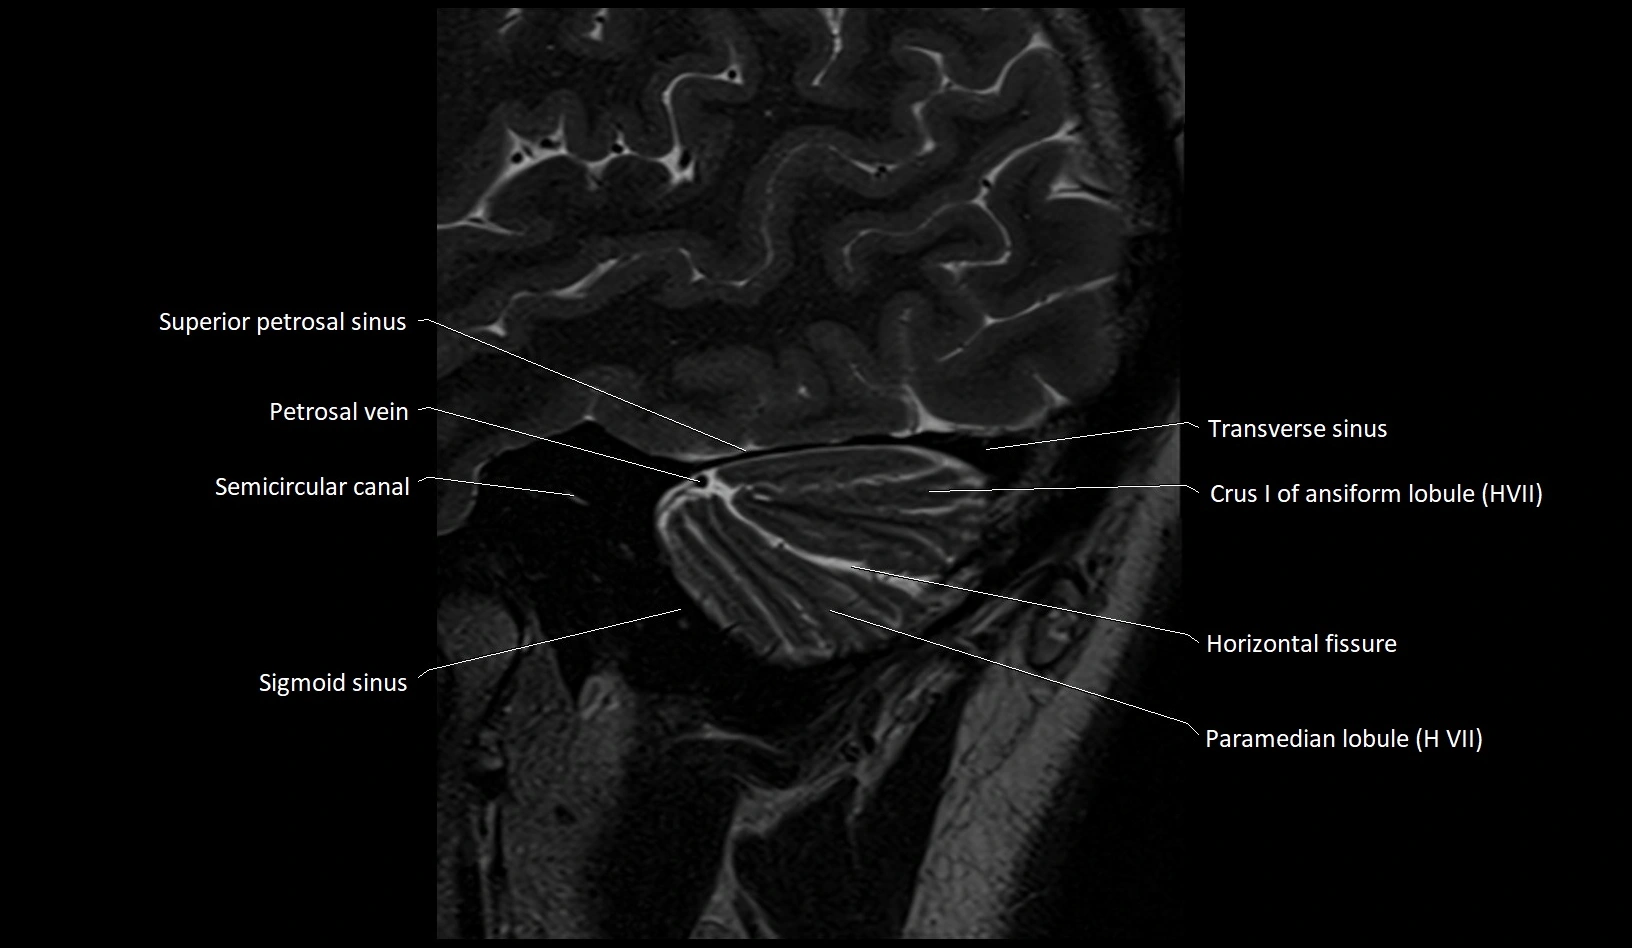

- Crus I of ansiform lobule of cerebellum

- Horizontal fissure (cerebellum)

- Paramedian lobule

- Paramedian lobule (HVII) of cerebellum

- Petrosal vein

- Semicircular Canals

- Sigmoid sinus

- Superior petrosal sinus

- Transverse sinus